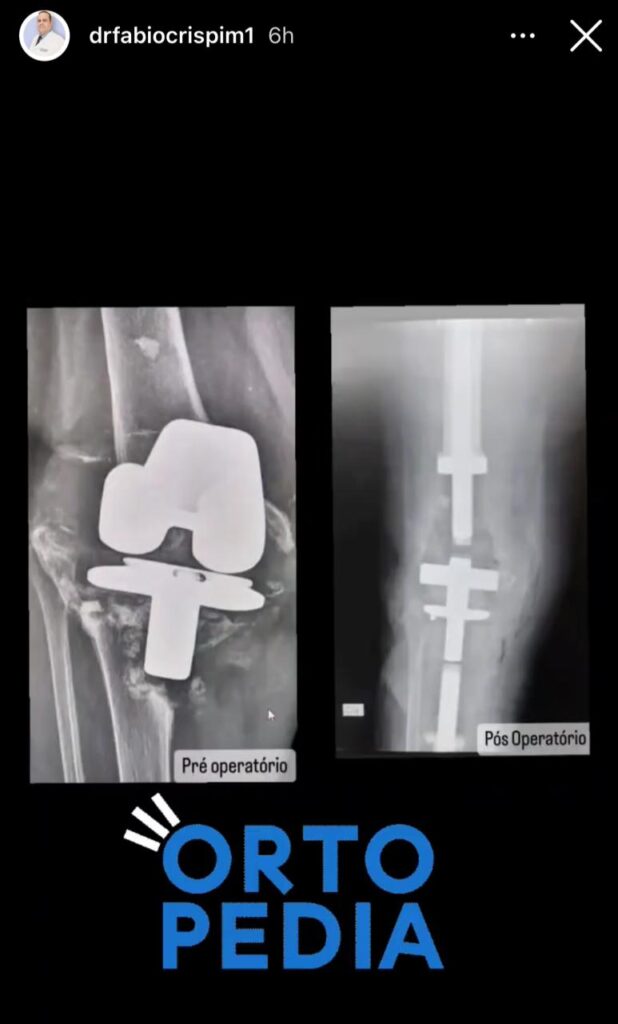

E, para a alegria de todos, na última sexta-feira, dia 15 de setembro de 2023, a Senhora Antonia Benedita da Cunha, natural de São Bento-PB, foi responsável por um feito inédito, uma vez que, foi A PRIMEIRA PACIENTE DA HISTÓRIA DO HOSPITAL DE TRAUMA DE CAMPINA GRANDE-PB A REALIZAR O PROCEDIMENTO CIRÚRGICO DE ENDOPROTESE DO JOELHO DIREITO.

Ademais, informamos que a são-bentense já está em fase de adaptação da prótese, sendo acompanhada por uma equipe de fisioterapeutas e médicos ortopedistas, e, nos próximos dias, receberá alta hospitalar e retornará a sua terra natal, São Bento-PB.